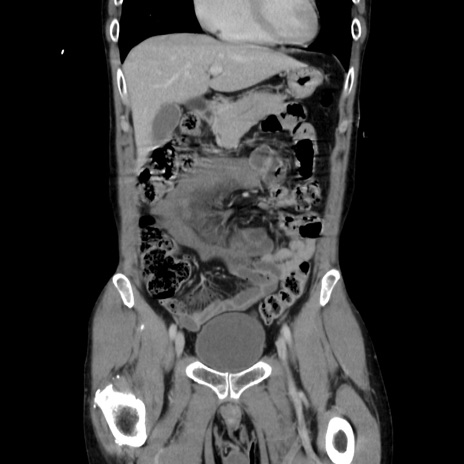

症例37(冠状断像)

【症例】40歳代 男性

【主訴】腹痛

【現病歴】4時間ほど前に電車に乗車中に臍部上より腹痛出現。徐々に増悪し起立困難となり、救急外来受診。生ものは数日食べていない。今朝お雑煮を食べた。

【身体所見】BT 36.8℃、BP 117/84mmHg、HR 91/min、SpO2 97%、苦悶様、腹部:臍上部広範囲圧痛あり、反跳痛±

【データ】WBC 8100、CRP 0.03